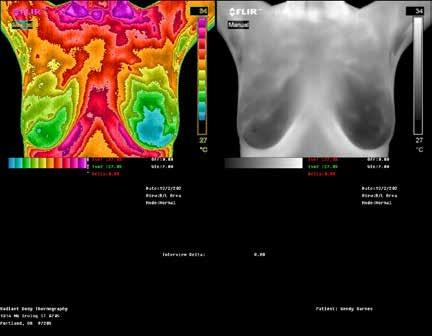

RADIANT BODY

THERMOGRAPHY

TOP: Thermographic pattern of physician confirmed estrogen dominance, which the client addresses. BOTTOM: Images show success in removing the estrogen dominance pattern & client also downgrades her abnormal right breast! Estrogen dominance has a heat signature visible with QUALITY Thermography.